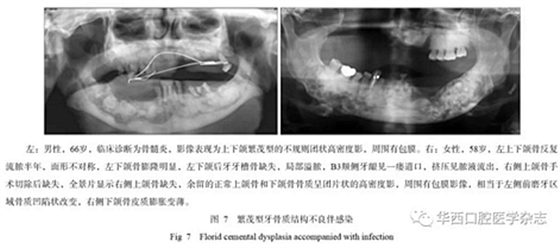

3.3牙骨質結構不良的影像學多樣性和與臨床的診斷相關性

牙骨質結構不良具有多樣性的影像學特征,所以在臨床上也表現(xiàn)為不同的癥狀,由于該疾病生長比較緩慢,患者在未出現(xiàn)癥狀前經(jīng)常不會來就診。當患者出現(xiàn)癥狀時或者醫(yī)生偶然在拍攝片子后發(fā)現(xiàn)根尖暗影,就會遇到診斷的問題,最常造成診斷不清的是診斷為慢性根尖周炎,按照慣性思維往往首先思考根尖周炎,就采用傳統(tǒng)的根管治療方式進行治療,但治療以后發(fā)現(xiàn)根尖的骨質改變更加明顯,極端的甚至出現(xiàn)長時間的癥狀不消失或者不愈,或者形成骨髓炎改變。多發(fā)性或者泛發(fā)性的牙骨質結構不良常常造成牙脫落或者拔牙后出現(xiàn)感染,進而出現(xiàn)骨髓炎改變,頜骨骨皮質密度增高、增厚,為炎性反應性增生所致(圖7)。

發(fā)生于后牙的牙骨質結構不良常常表現(xiàn)為頜骨膨脹,臨床容易診斷為腫瘤,牙骨質結構不良以往被稱為“假性牙骨質瘤”就可以表明這類腫瘤的特性,并且往往造成誤診,而病理由于組織切取和牙、骨等硬組織的原因,常常診斷也比較困難,需要結合X線檢查來確定[1]。對于泛發(fā)性的牙骨質結構不良,X線的診斷應該更具有優(yōu)勢,尤其是全景片可以清楚地顯示上下頜骨的病變,對于影像的相似性判斷更加容易,而CBCT的優(yōu)勢在于可以清楚了解病變區(qū)內(nèi)的結構、密度、邊界及相鄰牙等結構受影響的變化情況。